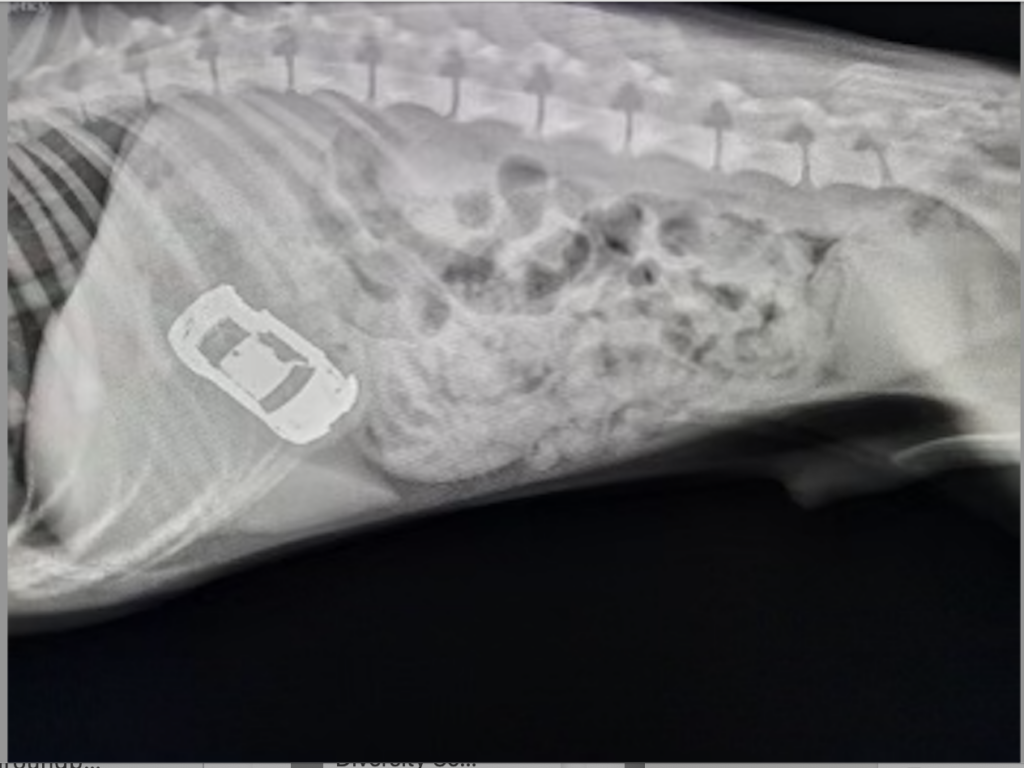

During the holidays, people will often package candy in holiday wrapping paper and put it under the tree. This is dangerous for pets — both the candy and the wrapping paper. Most candy is not great, but Cavanagh suggests keeping an eye out for anything with chocolate or raisins. Chocolate is particularly poisonous, and raisins can cause kidney injuries. The wrappers are problematic, too; wrappers can block an animal’s intestines and lead to a surgical emergency.